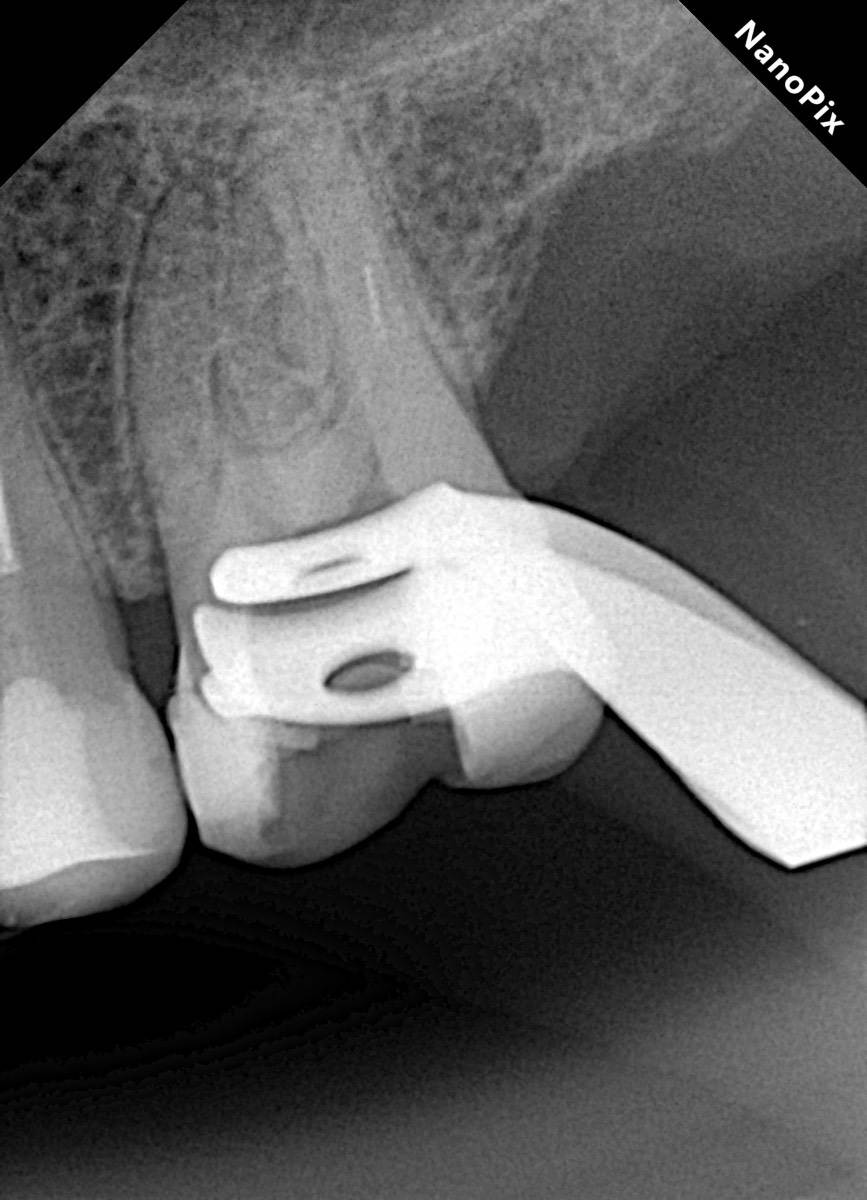

Гарриевич Опубликовано 18 марта Автор Поделиться Опубликовано 18 марта В 13.03.2026 в 15:26, Doc сказал: Круто! То, что вынимается, доктору вернуть надо или в металлолом сдать? :))) Обычно мы сдаем в чернмет, какие никакие деньги)) Реколл 3 года 1 Ссылка на комментарий

Гарриевич Опубликовано 3 апреля Автор Поделиться Опубликовано 3 апреля Еще один осмотр спустя 3 года и полное заживление 2 1 Ссылка на комментарий